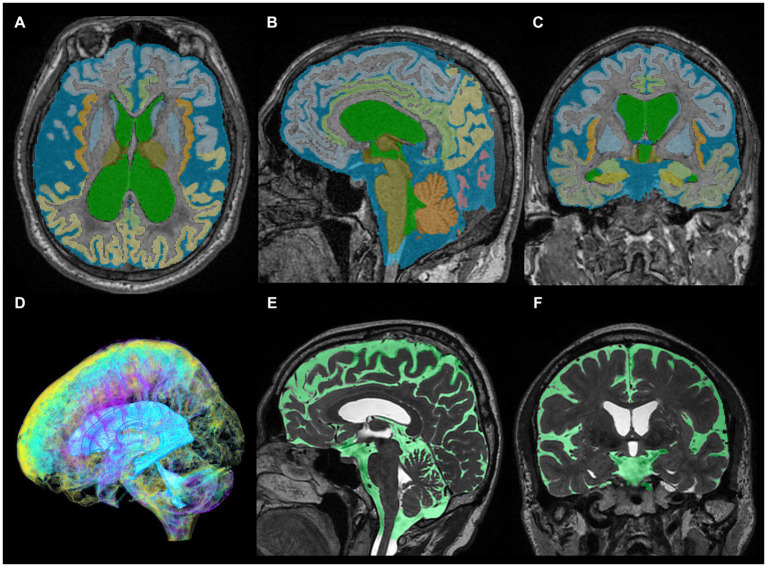

As ground truth labels in our AI models, input image masks for volumetric semantic segmentation on the 3D T1-weighted MRI were created by combining manual segmentation with the 3D Viewer and fully automatic segmentation with the Brain Subregion Analysis applications (Figures 1A–C) on an independent 3D volume analyzer workstation (SYNAPSE 3D; FUJIFILM Corporation, Tokyo, Japan). In the Brain Subregion Analysis application, intracranial spaces were segmented fully automatically into 26 subregions including ventricles and SAS within 1 min (ref. Yamada et al., 2023c). The input image masks from 3D T2-weighted MRI were also created using our original method, combining a simple threshold algorithm and manual segmentation (Figures 1D–F), as previously reported (ref. Yamada et al., 2015, ref. 2016a,ref. b). Total SAS were further segmented into the Sylvian fissure and basal cistern, and the high-convexity SAS, which was defined as the location above the body of the lateral ventricles, with the lateral end 3 cm from the midline, the posterior end in the bilateral posterior parts of the callosomarginal sulci, and the anterior end on the coronal plane perpendicular to the AC–PC line passing through the front edge of the genu of the corpus callosum (Figure 2; Supplementary Videos S1–S4) (ref. Yamada et al., 2023a). All input image masks as the ground truth labels were transferred to the SYNAPSE Creative Space for cloud-based AI development service (FUJIFILM Corporation). All masks were processed and formatted into a form that could utilize the training or inference process. Regarding the output of the inference process, feature maps were obtained. Overall, 159 T1-weighted images were assigned to 110 images for training, 30 for internal and 19 for external validation (test), and 180 T2-weighted images were assigned to 130 images for training, 30 for internal validation and 20 for external validation. Inference was performed in the images for internal validation and external validation.